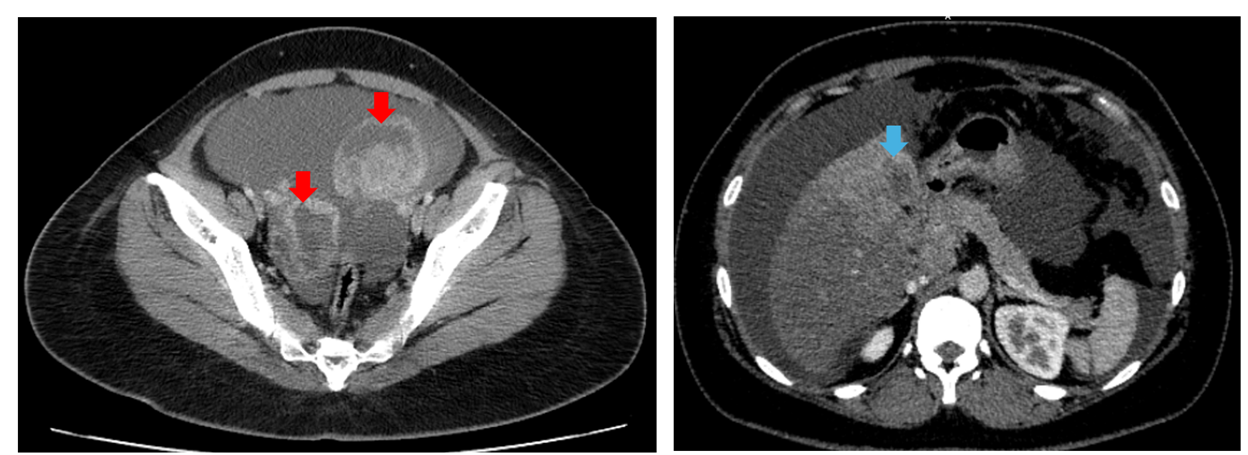

Hình 1: Chụp CT ổ bụng: Hình ảnh tiểu khung hai bên có cấu trúc hỗn hợp, gồm phần dịch và phần nang, lớn nhất kích thước ~50x70mm (mũi tên đỏ). Nhu mô gan hạ phân thùy IV có khối kích thước 28x33mm, sau tiêm ngấm thuốc vỏ,  theo dõi thứ phát, nhu mô gan lân cận, có nốt đường kính ~5mm, ngấm thuốc thì động mạch (mũi tên xanh)